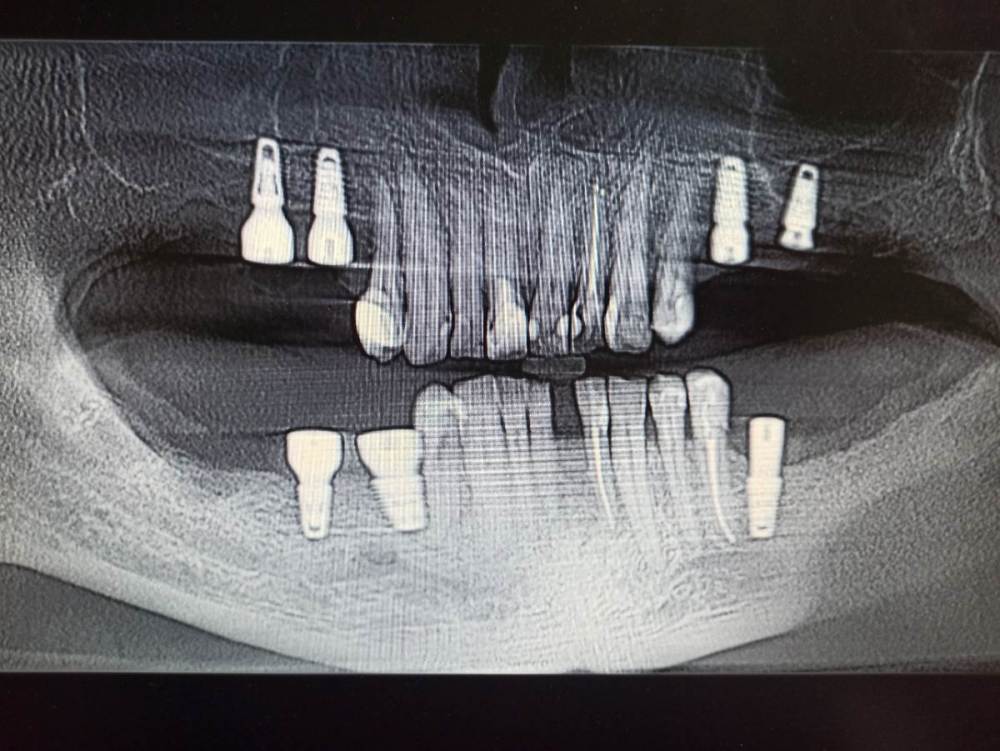

Roma0018 Опубликовано 6 марта, 2023 Поделиться Опубликовано 6 марта, 2023 Хочу узнать мнение специалистов. Правильно ли установлены импланты ?? Ссылка на комментарий

red_butler Опубликовано 7 марта, 2023 Поделиться Опубликовано 7 марта, 2023 Это панорамная реконструкция из Кт, на ней есть геометрические искажения. позиции имплантов правильные. Ссылка на комментарий